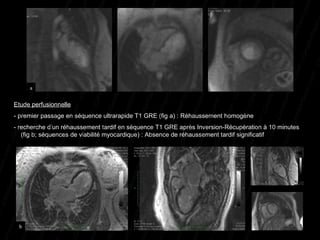

Etude perfusionnelle   - premier passage en séquence ultrarapide T1 GRE (fig a) : Réhaussement homogène - recherche d’un réhaussement tardif en séquence T1 GRE après Inversion-Récupération à 10 minutes    (fig b; séquences de viabilité myocardique) : Absence de réhaussement tardif significatif a b